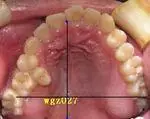

双尖牙